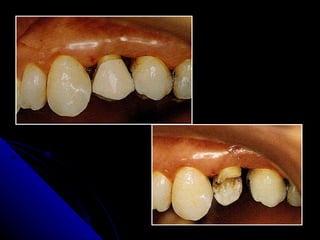

LIMITE CERVICAL  Nas   restaurações subgengivais  com muita freqüências observa-se inflamação gengival, placa bacteriana e formação de bolsas periodontais .